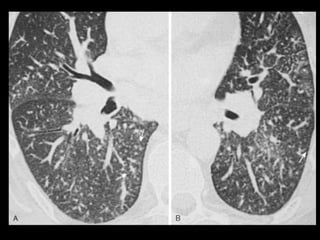

Êmbolo Séptico TC: modalidade importante para confirmar a presença de êmbolos sépticos quando a radiografia convencional de tórax permanece negativa; TC: nódulos bilaterais mais numerosos nas regiões periféricas dos pulmões e nas bases; Os nódulos podem ser bem circunscritos ou mal definidos e com frequência apresentam escavações; O sinal do vaso nutriz pode estar presente em 60- 70% dos casos.

• 48.

Aspergilose broncopulmonar invasiva A aspergilose broncopulmonar angioinvasiva é a infecção pulmonar fúngica mais comum; Fatores de risco maiores são: neutropenia severa ou prolongada(<500 células), terapia prolongada com corticoides, doença enxerto versus hospedeiro após TMO alogênico e estágios tardios de SIDA; Sintomas não específicos: febre, tosse e dispneia; Diagnóstico: dados clínicos, radiológicos e micológicos.